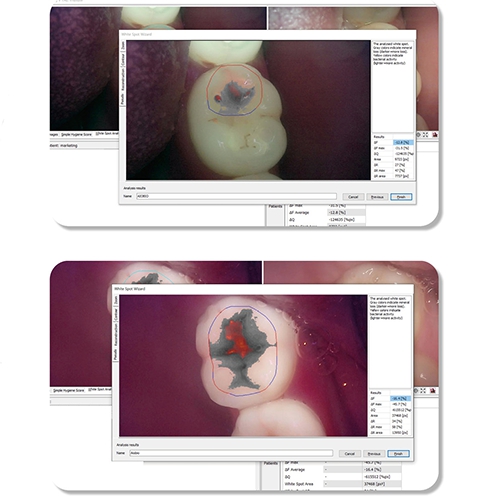

또한 병원과 환자 그리고 질병과 건강을 이어주는 구강건강관리서비스 LinkDens를 통해 치과의사 임상 판단과 AI기반 영상분석에 따른 평가와 기록을 하는 치아위험도 및 구강관리도 평가를 제공하고, 앱으로 검사결과지 확인, 예약관리, 구강상태관리를 활용하는 구강관리서비스를 신사업분야로 확장하고자 합니다.

무기질 변화량고 세균 활성도를 정량화해 분석 (큐레이캠 Pro 또는 큐레이펜 C와 함께 사용) |